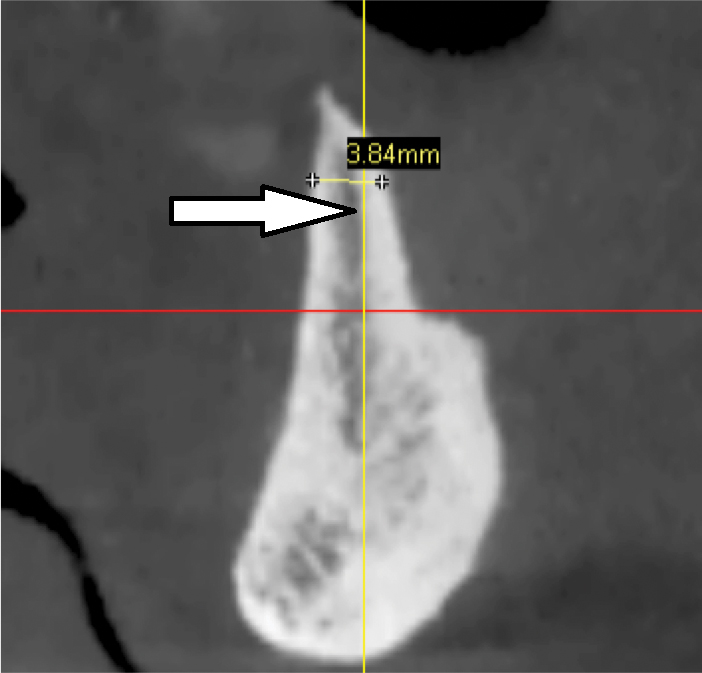

Fig 8. Deficient ridge contour at the osseous crest: cross-sectional view. This ridge (arrow) is not wide enough to receive an implant unless additional bone grafting is done to accommodate the implant’s width or the bone is reduced to a widened part of the ridge suitable for implant insertion.

Figure 8